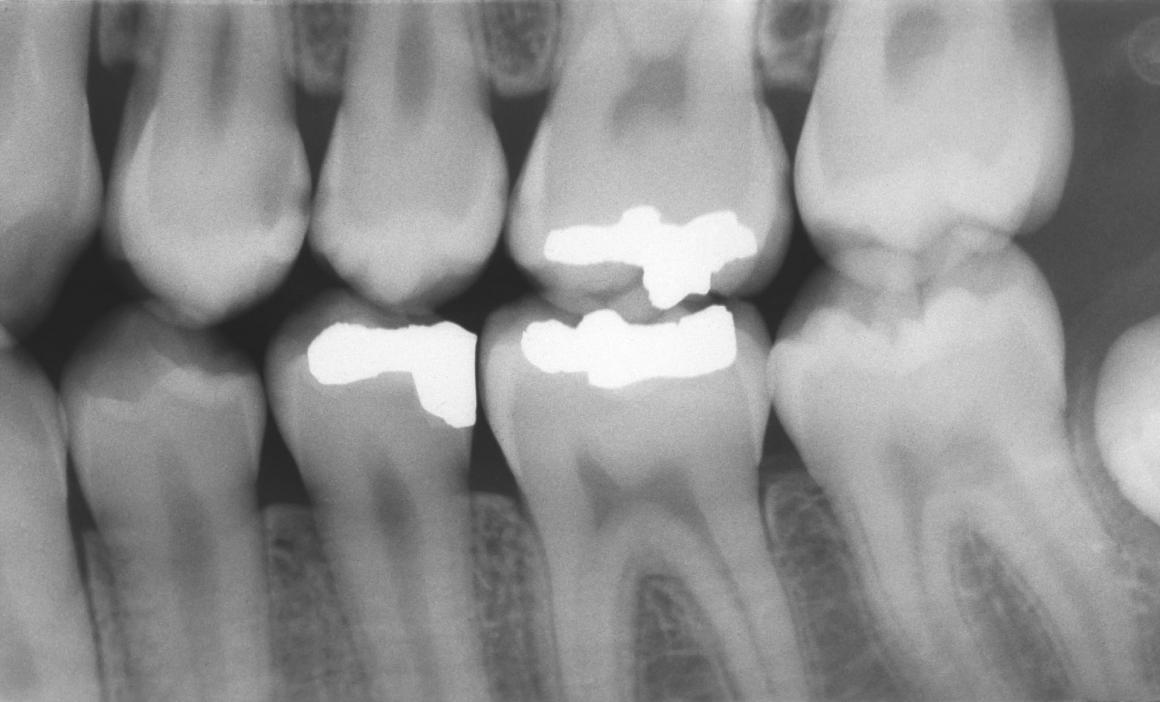

Die klinische Untersuchung, insbesondere die visuelle Inspektion mit Puster und Spiegel sind Standard. Zusätzlich dienen Röntgenbilder z.B. Bißflügel zur Kariesdiagnostik und damit zur Entscheidung, ob ein Zahn oder eine Zahnfläche eine Restauration benötigt.